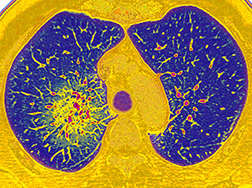

Pulmonary Hypertension

The Pulmonary Hypertension Centers of NewYork-Presbyterian are among the largest programs in the world for pulmonary hypertension, caring for patients with idiopathic and heritable pulmonary hypertension and those with medical conditions that predispose them to its development. Accredited by the Pulmonary Hypertension Association as Pulmonary Hypertension Centers of Comprehensive Care, the Heart Failure and Pulmonary Hypertension Services in the Perkin Center for Heart Failure of NewYork-Presbyterian/Weill Cornell Medical Center and the Pulmonary Hypertension Comprehensive Care Center of NewYork-Presbyterian/Columbia University Irving Medical Center manage some of the most complicated and sickest patients with this rare, progressive cardiopulmonary disease.

Pulmonary hypertension and right heart failure complicate the management of about one-third of the patients with heart failure. Our cardiologists provide management strategies for all aspects of pulmonary hypertension, be they idiopathic or hereditary; connective tissue disease; congenital heart disease-associated PAH [WHO Group 1]; or a consequence of left-sided heart disease, such as heart failure reduced or preserve ejection fraction, cardiomyopathy, or valvular heart disease; lung or hypoxic related; or chronic thromboembolic disease related pulmonary hypertension. The nuances and subtleties involved in advanced heart failure require the expertise of a multidisciplinary, collaborative center.